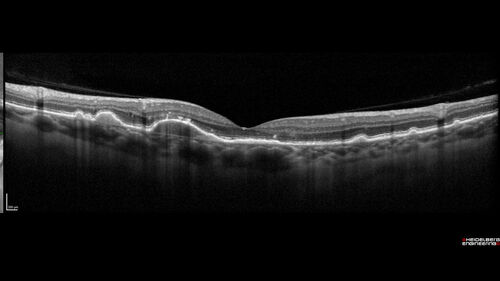

Dry AMD - Pigment - AREDS risk score of 4

65 year old woman with 20/32 vision. A little blurred. Pigment and large drusen in each eye. AREDS risk score of four.